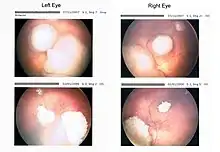

Drawing of a large retinoblastoma

Aspect of trilateral retinoblastoma on MRI

Funduscopic finding of a retinoblastoma

Ocular fundus aspect of retinoblastoma

Large exophytic white tumor with foci of calcification producing total exudative retinal detachment